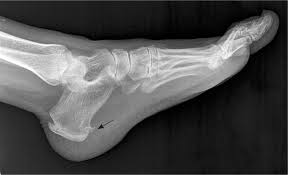

Baxter Neuropathy Radiology Reference Article Radiopaedia Org

Baxter Neuropathy Radiology Reference Article Radiopaedia Org from prod-images-static.radiopaedia.org